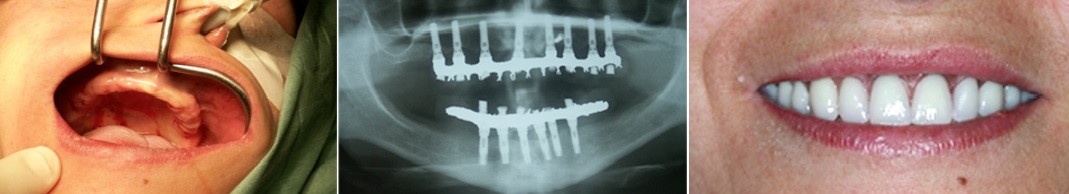

Imagen en alta resolución. Este enlace se abrirá mediante lightbox, puede haber un cambio de contexto"En los casos en los que la pérdida de hueso es en anchura, debemos recurrir a los injertos óseos en bloque. Se trata de obtener pequeños fragmentos de hueso que serán fijados a los maxilares, de forma que la anchura de éstos se verá incrementada. La fijación se realiza mediante pequeños tornillos y en un periodo de 4 a 6 meses podremos colocar los implantes", indica el doctor.

Imagen en alta resolución. Este enlace se abrirá mediante lightbox, puede haber un cambio de contextoPara estos casos tan severos, señala Manuel Chamorro, se han desarrollado 2 técnicas diferentes: "Por un lado los implantes cigomáticos que se trata de unos implantes más largos que los habituales que se insertan en el hueso cigomático (hueso del pómulo) y se pueden combinar con implantes convencionales. Pueden colocarse 2 cigomáticos en combinación o 4 implantes cigomáticos que pueden ser suficientes para colocar una rehabilitación dental completa y fija".

Y por otro, según el experto, recientemente se ha introducido y desarrollado los implantes subperiósticos a medida. "En este caso se trata de una estructura, diseñada a medida, que abraza, se adapta y se fija íntimamente al hueso por su cara externa. Por tanto, la estructura no entra en el hueso, sino que se apoya en su superficie. Esta estructura se diseña a medida de cada maxilar previa realización de un TAC 3-D. De la estructura emergen unos cilindros que salen a través de la encía y fijan la prótesis dental".

Para el Dr. Manuel Chamorro, las ventajas de esta técnica son evidentes: permite colocar prótesis dentales fijas en maxilares muy atróficos de una manera sencilla. La prótesis dental se coloca el mismo día, ya que no hay que esperar un tiempo de osteointegración. No se invade el seno maxilar. Por lo que puede realizarse sin problemas incluso en pacientes que han sufrido sinusitis.